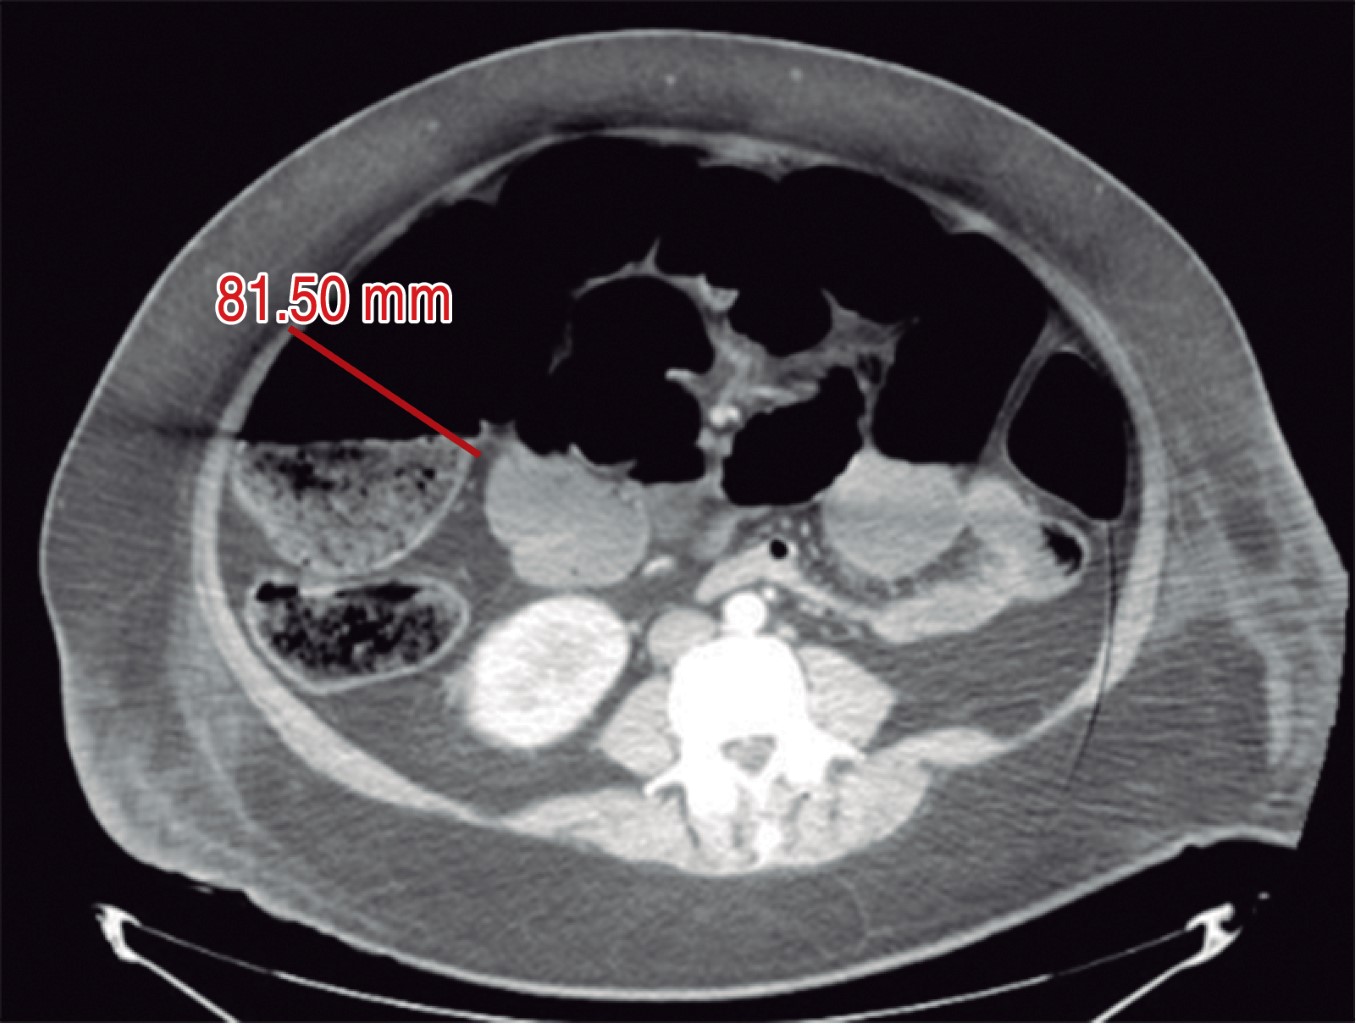

Mujer de 39 años con antecedente de diabetes mellitus tipo 2, hipertensión e hipotiroidismo, acudió a urgencias con quemaduras superficiales y profundas (segundo y tercer grado) en la cara (Figura 1), brazo derecho y extremidades inferiores circunferenciales (Figuras 2 y 3). Se realizó fibronasoendoscopia por otorrinolaringología y se descartó quemadura de la vía aérea. Se calculó la superficie corporal total quemada en 24%, se administró líquidos con la fórmula de Parkland con solución Hartmann 950 mL/h durante las primeras ocho horas, con diuresis a 0.5 mL/kg/h. La paciente fue ingresada en el piso de cirugía plástica para seguimiento. Al segundo día se quejó de dolor y distensión abdominal, por lo que se tomaron radiografías de abdomen (Figura 4) que revelaron distensión intestinal. Se decidió realizar tomografía computarizada que mostraba distensión de hasta 8.5 cm en colon (Figura 5), sin evidencia de obstrucción mecánica. Los electrolitos séricos eran normales. Se decidió dar manejo conservador en piso por 72 horas, con mejoría clínica. Se retiró la sonda nasogástrica y toleró la dieta. Se vigiló por 48 horas y se decidió su egreso por mejoría clínica. Acudió a consulta 10 meses después, negando cuadros de dolor abdominal y tolerando la vía oral. Se encontraba en rehabilitación por las quemaduras.

Como cirujanos plásticos y reconstructivos es importante conocer las causas relacionadas con la pseudoobstrucción de colon aguda para sospechar de esta entidad, ya que el reconocimiento temprano y buen manejo de esta patología reducirá la morbimortalidad de nuestros pacientes. El manejo conservador es el de elección en el síndrome de Ogilvie. El estudio de imagen ideal es la tomografía contrastada de abdomen para valorar un posible sitio de oclusión o complicación. En nuestro caso, la paciente tuvo un buen resultado con el manejo conservador. Es importante conocer esta etiología y reportarla en pacientes quemados.

Figura 5